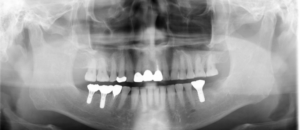

では、初診時の口腔内写真とレントゲン写真です。

初診時

右下インプラント埋入直後のレントゲン写真です。

矢印部に下顎内の神経があり、これを避け、隣の歯と十分距離が保てるような位置でインプラントを埋入できました。